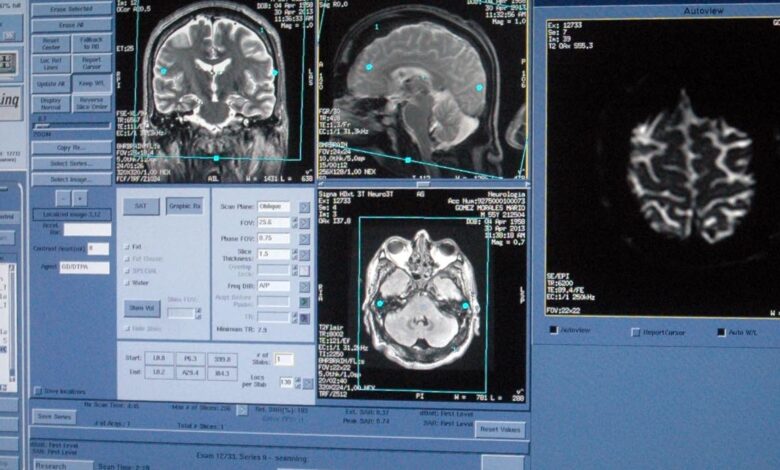

Respecto al diagnóstico, por lo general no se necesitan pruebas específicas; no obstante, existen pacientes que son sometidos a estudios de resonancia magnética de la columna cervical y otros, porque presentan un cuadro clínico indefinido.